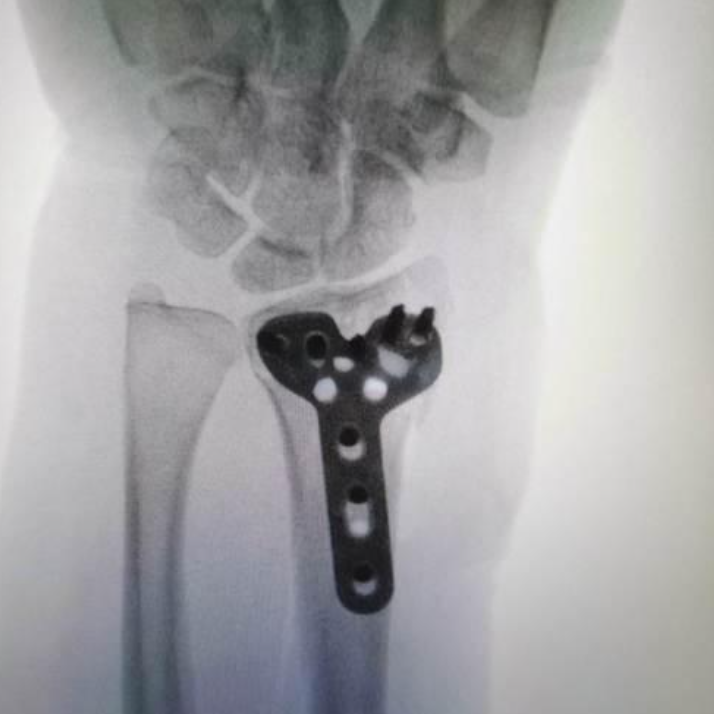

術后(hou)病例(li)圖片

橈骨(gu)(gu)遠端骨(gu)(gu)折手術(shu)解決(jue)方案